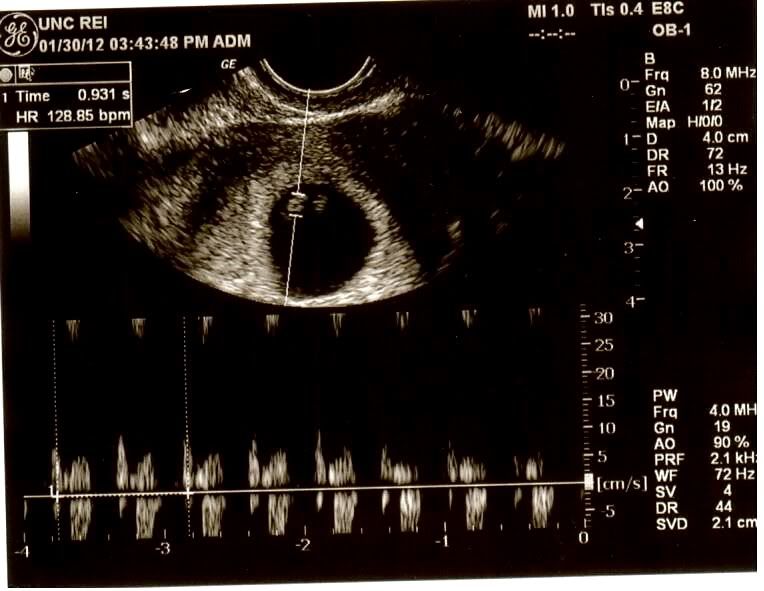

Our little peanut measuring 6 weeks 2 days!

Our baby had a HR of 129! This picture shows the heart beating..

We go back in 1 week for another ultrasound and then we will be released! We are sooooooooooooo excited!~Cheryl and Frank~ 06/28/08